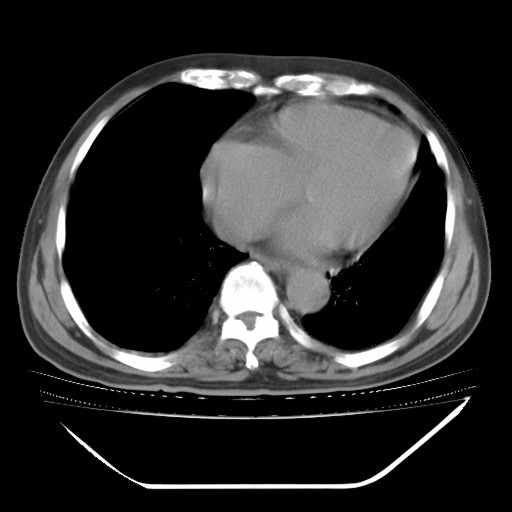

以下是引用hhcckk在2009-5-29 10:34:00的发言:[br]左下肺片絮状边缘模糊影,考虑感染,建议治疗后复查[br]